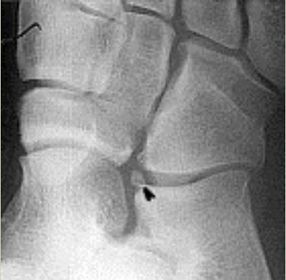

What disease is this? What causes it? | Brodie's abscess - chronic bone abscess caused by organisms of low virulence. Patient most likely did not go through an acute phase (just chronic osteo) |